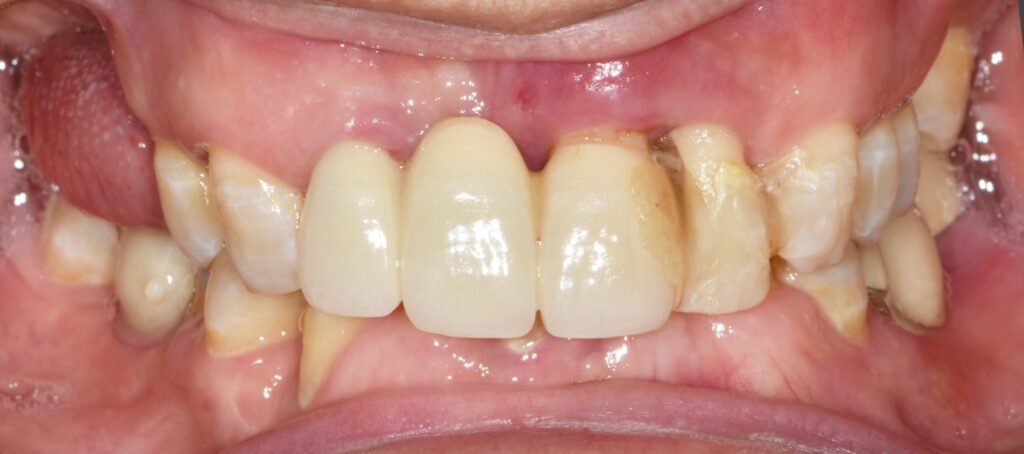

그리고 앞니 임플란트까지 잘 심어드렸네요.

어금니를 든든하게 만들어 드렸고 어금니와 앞니가 상호 보호하는 역할을 수행할 수 있도록 보철 과정을 잘 진행했습니다.

​6개월 검진 오셨는데 불편한 점 없이 잘 쓰고 있다고 고맙다고 인사 전해주셨네요.^^